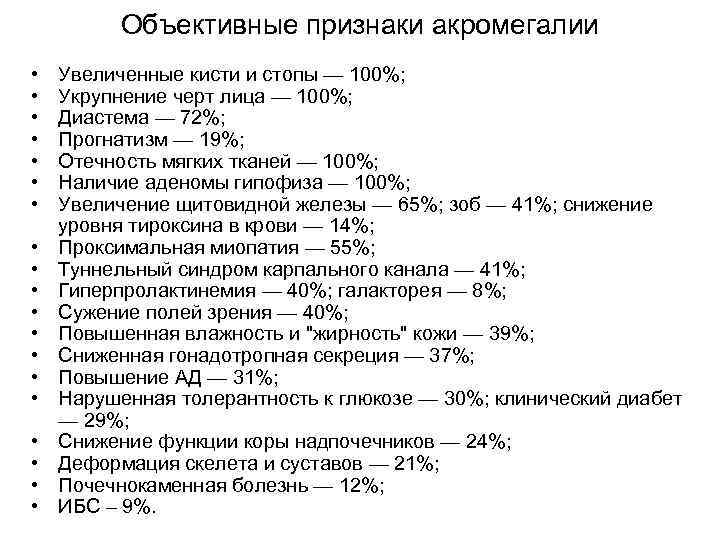

Объективные признаки акромегалии • • • • • Увеличенные кисти и стопы — 100%; Укрупнение черт лица — 100%; Диастема — 72%; Прогнатизм — 19%; Отечность мягких тканей — 100%; Наличие аденомы гипофиза — 100%; Увеличение щитовидной железы — 65%; зоб — 41%; снижение уровня тироксина в крови — 14%; Проксимальная миопатия — 55%; Туннельный синдром карпального канала — 41%; Гиперпролактинемия — 40%; галакторея — 8%; Сужение полей зрения — 40%; Повышенная влажность и "жирность" кожи — 39%; Сниженная гонадотропная секреция — 37%; Повышение АД — 31%; Нарушенная толерантность к глюкозе — 30%; клинический диабет — 29%; Снижение функции коры надпочечников — 24%; Деформация скелета и суставов — 21%; Почечнокаменная болезнь — 12%; ИБС – 9%.

Объективные признаки акромегалии • • • • • Увеличенные кисти и стопы — 100%; Укрупнение черт лица — 100%; Диастема — 72%; Прогнатизм — 19%; Отечность мягких тканей — 100%; Наличие аденомы гипофиза — 100%; Увеличение щитовидной железы — 65%; зоб — 41%; снижение уровня тироксина в крови — 14%; Проксимальная миопатия — 55%; Туннельный синдром карпального канала — 41%; Гиперпролактинемия — 40%; галакторея — 8%; Сужение полей зрения — 40%; Повышенная влажность и "жирность" кожи — 39%; Сниженная гонадотропная секреция — 37%; Повышение АД — 31%; Нарушенная толерантность к глюкозе — 30%; клинический диабет — 29%; Снижение функции коры надпочечников — 24%; Деформация скелета и суставов — 21%; Почечнокаменная болезнь — 12%; ИБС – 9%.